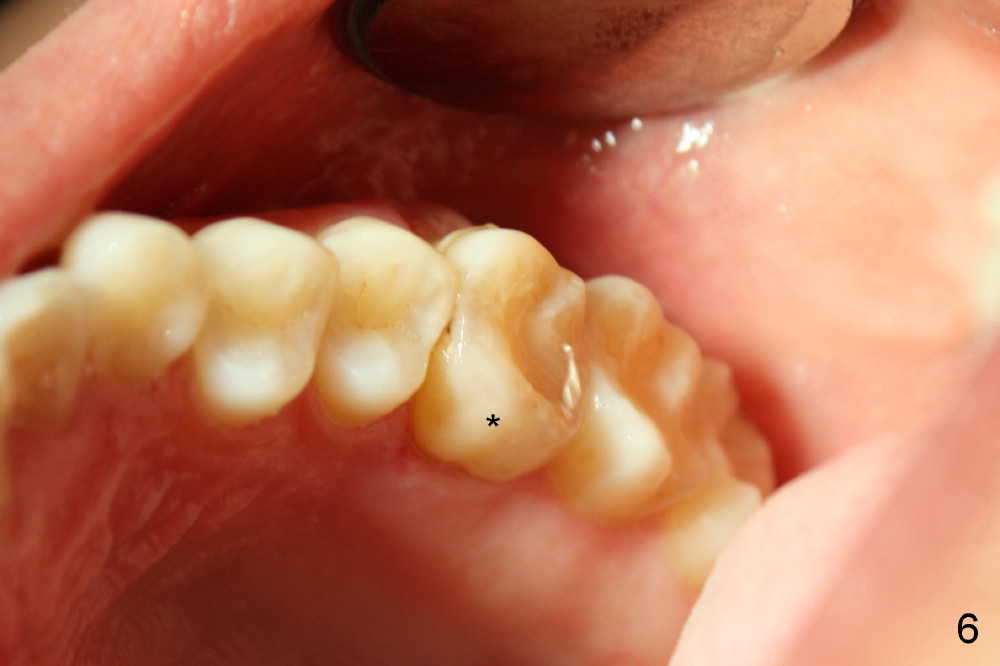

两周后,右下牙冠粘固,稍微调合,牙冠合面就穿孔了,向病人赔礼道歉,只好再预约重做,病人不满意的地方是牙冠与邻牙之间食物坎塞,重做牙冠还可能不能解决问题,只有矫正才能改变牙齿位置,倾斜度,而改正牙齿之间接触关系。不过先做左上,左下牙冠,制作也不容易,图六显示术前左上第一磨牙(*),好像supraeruption不厉害,但是咬合观显示左上第一磨牙的确往下移动不少(图七),星号(*)代表左下临时牙冠。没有任何其它选择,只好大刀阔斧磨左上第一磨牙(图八),这次大刀阔斧心情可不好,很辛苦。检查咬合,发现上下空间太大了(图九箭头),上次磨下颌基牙时太过分了。